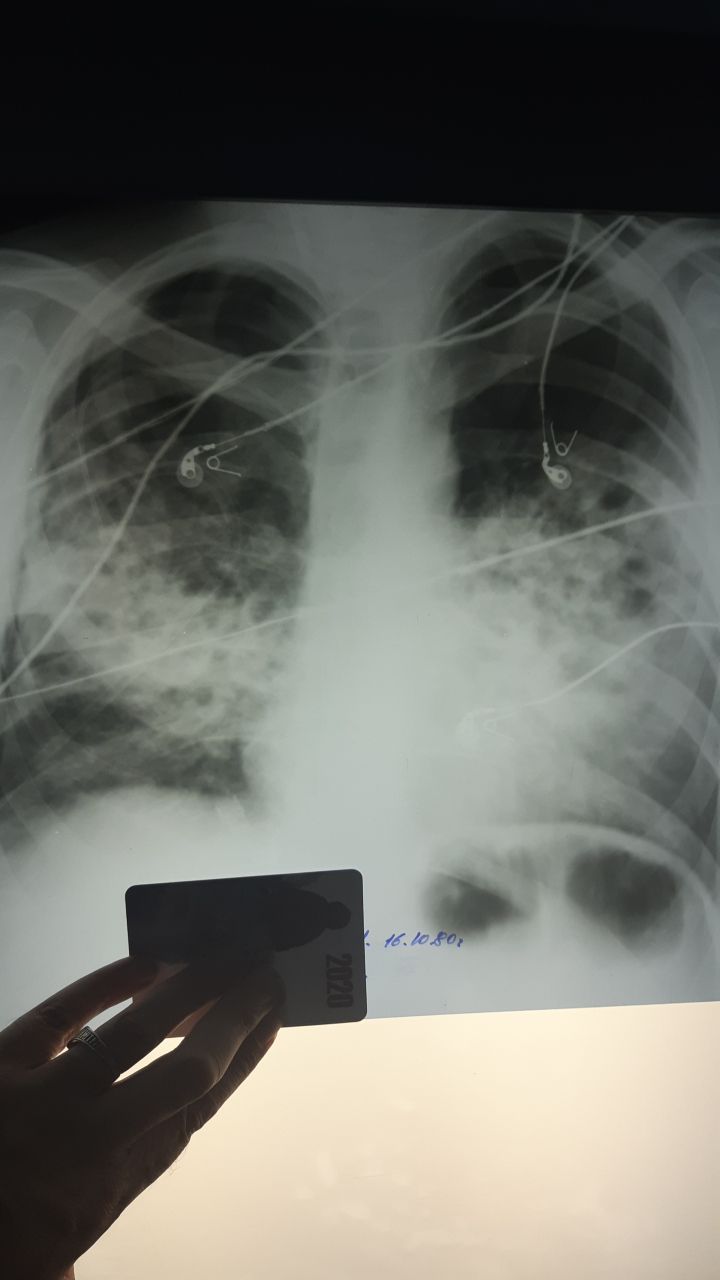

Описал как посттуберкулезные изменения верхушек и патология левого корня+ гипоплазия сердца СЛК=30%

Легочное сердце не такое? При длительном хроническом туб процессе встречал у пациентов

Каплевидная конфигурация

Это за счёт эмфиземы и изменения формы грудной клетки- сердце занимает вертик положение

Классическое ХЛС- увеличение правых отделов

Это не легочное сердце это подразумевается наличие гипоплазии,возможно и синдром Морфана

Ковид+ вич

Булыжная мостовая